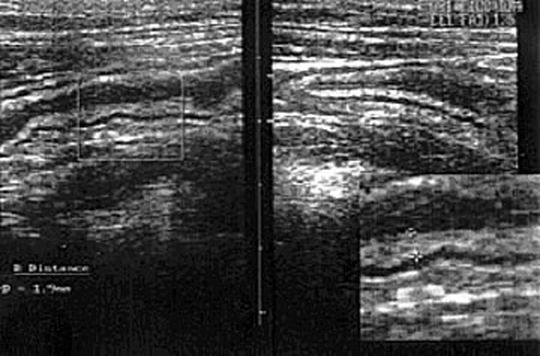

5.7. Lesiones inflamatorias o isquémicas